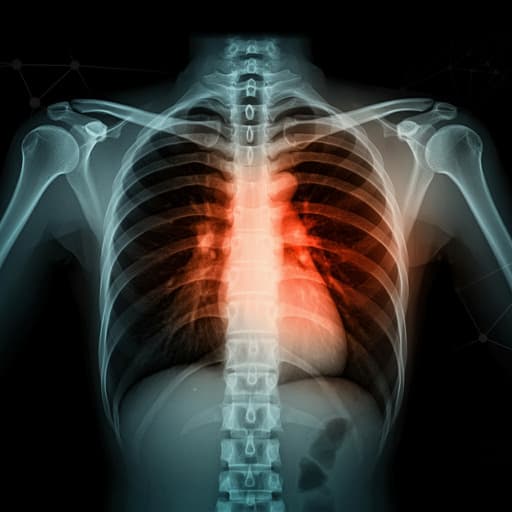

COVID-19 Prognosis from Chest X-ray Images by using Deep Learning Approaches: A Next Generation Diagnostic Tool

This exciting research conducted by Madhumita Pal, Smit Parij, Ganapati Pan, Snehasish Mishra, Ranjan K Mohapatra, and Kuldeep Dhama explores the powerful application of deep learning models, VGG-16 and LSTM, for accurate COVID-19 diagnosis from chest X-ray images. The findings illustrate impressive classification accuracy, making it a promising tool for swift COVID-19 screening in challenging environments.